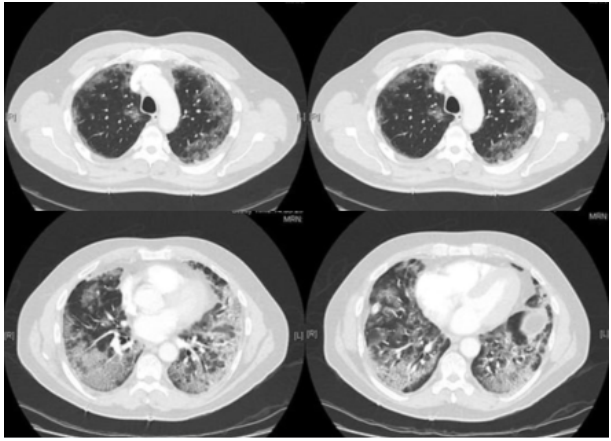

病例1::60岁男性,不吸烟,无其他疾病病史。感染新冠病毒后胸闷憋喘,遂至医院急诊就诊,测指氧饱和度为88%,动脉血气分析(FiO2 35%):pH 7.50,PaO2 51 mmHg,PaCO2 31.5 mmHg,HCO3- 26.6 mmol/L,BE 2.5 mmol/L,Lac 2.2 mmol/L。胸片示双下肺广泛磨玻璃影(图2)。入院1天后,患者氧合下降明显,需氧量增加,完善CT肺动脉造影(CTPA)检查未发现肺栓塞,广泛的磨玻璃改变及小叶间隔增厚(图3)。予地塞米松6 mg/d;病房清醒俯卧位,时间超过18 h/d,仰卧位时,患者反复出现低至82%的血氧饱和度,在不改变吸氧浓度情况下继续俯卧位,就能将其纠正至94%。患者最终好转出院,出院时血氧饱和度达到95%。病例2::35岁男性,轻度持续性哮喘、肥胖、阻塞性睡眠呼吸暂停(OSA)病史,因胸闷憋喘3 d入院,无发热、咽痛等不适。入院后因氧合不能维持行气管插管,同时予静脉糖皮质激素、利尿、扩张支气管治疗,7 d后顺利拔管。拔管后出现需氧量上升,但无其他感染征象及证据,氧合指数80 mmHg,吸氧浓度约80%。由于焦虑及不适,患者俯卧位仅能持续5 min,予阿普唑仑和俯卧位后,患者第2天可俯卧位2 h,俯卧位1 h时,吸氧量可将至40%,且在仰卧位后需氧量未再增加。